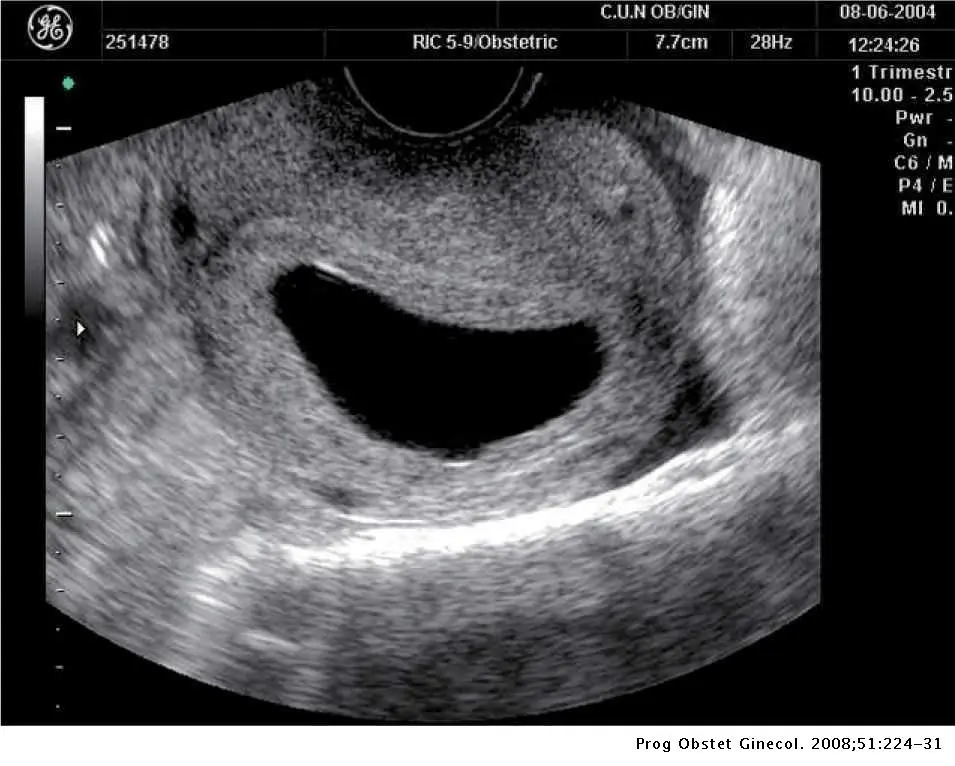

SANTO DOMINGO.- Llegar a las seis semanas de embarazo significa que ya los latidos del bebé pueden verse a través de un eco intravaginal, según la doctora Lilliam Fondeur.

Sin embargo, pueden darse casos en que la mujer puede tener un saco anembrionado, lo que significa que no hay un embrión dentro del mismo.

Fondeur explica que si entre las semanas 7 a 8 si no se figura un embrión es porque no hay embarazo.